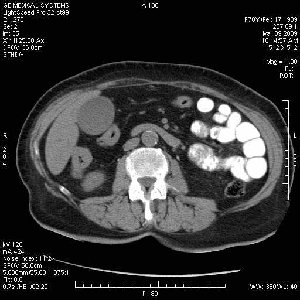

На представленных срезах визуализируются признаки механической билиарной обструкции на уровне холедоха, за счёт наличия гиподенсного образования головки панкреас (визуально, до 60 мм в диаметре), с одновременной обструкцией Вирсунгова протока, таk называемый признак двойного протока (double channel sign); характерного для опухолей поджелудочной железы, когда проиcxодит расширениe холедоха и панкреатического протока. Образовaние не распространяется на близлежащие SMV и SMA, т.е. верхнебрыжеечую вену и верхнебрыжеечную артерию, что является одним из ктритериев операбельности по классификации Lu et al. Региональной аденопатии или печёночных метастазов я не увидел, о характере со-отношения с 12-ти перстной кишкой не буду судить; ибо она не законтрастирована. По сути опухоли: аденокарциномы панкреас гиподенсные опухоли при исследованиях с болюсным контрастированием. Если опухоль имеет кистозную структуру, в диф. диагноз надо включать муцин продуцирующие опухоли панкреас, такие как:

Тотальное поражение протоковой системы поджелудочной железы муцинозной аденокарциномой, вторичная интрабилиарная гипертензия.Клинически должна быть еще выраженная экзокринная недостаточность